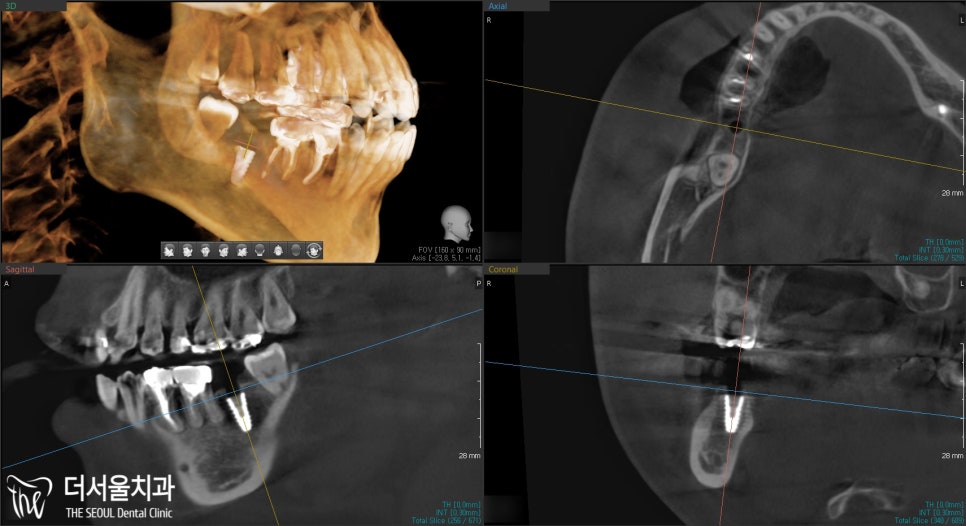

성남 치과 에서 수술 후

👉3D CT 를 통해

픽스처가 잘 심어졌는지 확인 결과,

올바른 위치와 각으로

식립된 것을 볼 수 있습니다.

이제 어느 정도 시간을 두고

기다렸다가 뼈와 픽스처 결합이

잘 이뤄진 뒤에 상부 보철물 세팅을

해드리면 됩니다.